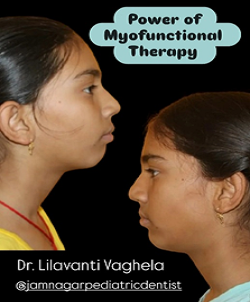

Case Report

Explore comprehensive case reports with findings, procedures, and summaries.